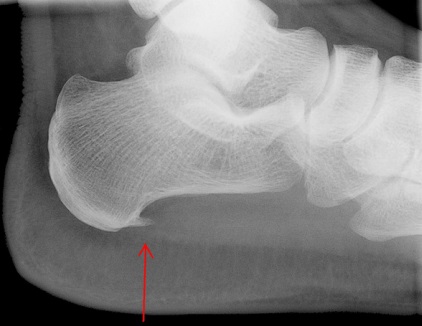

Η παχυσαρκία, η κύηση, η έντονη καταπόνηση στην άθληση, η χρήση παπουτσιών χωρίς καλή υποστήριξη αποτελούν προδιαθεσικούς παράγοντες ανάπτυξης φλεγμονής.                                                                          Συχνά μπορεί να διαπιστωθεί στην ακτινογραφία του άκρου ποδός η ύπαρξη άκανθας, η οποία συνιστά μια οστέινη προεξοχή σαν αγκάθι στην πτέρνα. Πρόκειται για εναπόθεση αλάτων λόγω χρόνιας υποτροπιάζουσας φλεγμονής της απονεύρωσης. Προκαλεί έντονο πόνο στην όρθια στάση και την βάδιση.